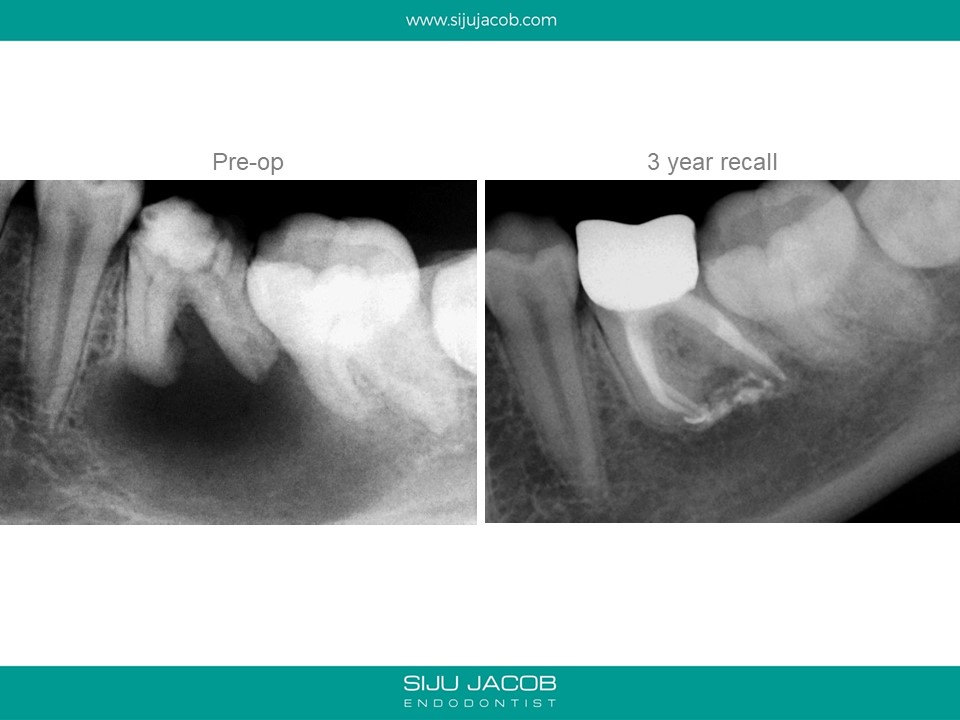

This was a 15 year old girl with a large peri-apical lesion in relation to the the left mandibular first molar. The tooth had a guarded restorative prognosis. The goal of endo in this case was to hold the tooth for a longer period before placing implants and also get some bone to fill in which would make implant placement more viable. I held the tooth with calcium hydroxide dressing for 5 months, saw some bone-fill and obturated the tooth. A crown was also placed. 3-year recall shows the tooth still going strong.